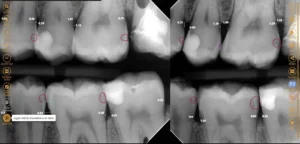

An x-ray taken three years later shows the healthy implant has integrated well with the bone around it. The implant looks stronger than ever and our patient is happy with the results.

A 3D scan was taken to measure the bone. Although a bit limited in space for an implant, there was enough space to place an implant if done very precisely.